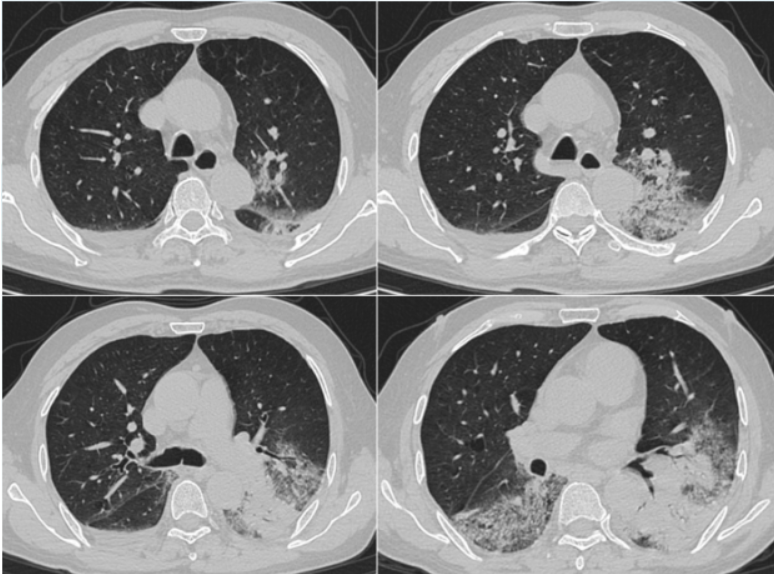

治疗后患者体温逐步恢复正常,炎症指标下降。复查胸部CT(2025-02-18)可见双肺炎症稍吸收(图3)。

图3 患者治疗前后胸部CT对比

2025年3月5日复查胸部CT病灶较前进展(图4),炎症指标有所回弹,以中性粒细胞升高为主,抗感染方案调整为哌拉西林他唑巴坦4.5 g q9h+奥马环素300 mg qd po。

图4 患者复查胸部CT对比

2025年3月12日患者氧合无明显改善,复查胸部CT示肺部病灶进展(图4)。将抗生素方案调整为美罗培南+米卡芬净+莫西沙星,甲泼尼龙抗炎,无创呼吸机辅助通气。